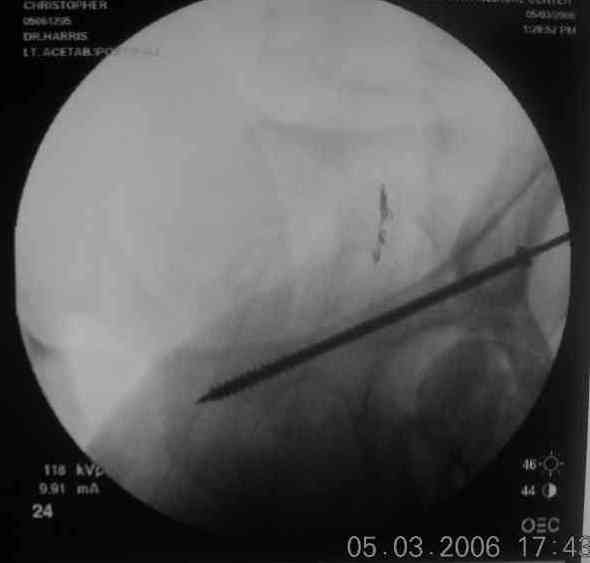

Here's a pic from the foot of the bed and you can see the clamp in the wound and the knee is extended so he must've had a tight rectus. The C-arm is rolled back to an obturator oblique image to reveal the anterior column...we put a slight outlet tilt to combine the images and give a better view of the anterior column...we can see the posterior column limb reduction in the wound, we can palpate the quadrilateral surface limb, and the image demonstrates the anterior column portion...you can adjust the tilt and rotation to image tangentially to the fracture plane if you'd like. We've inserted a 2mm K wire to site the starting point and aim/orientation for the drill and screw

Prone Imaging

OK, now we're inserting the drill percutaneosuy using a sleeve. This fluoro shot is not for this patient (notice no clamp) but I was too lazy to go searching the PACS for one with the clamp on, so pretend...I'll save the next ones and send along...the imaging is the same and the clamp doesn't obstruct imaging other than very rarely...you can always tilt the C-arm a bit to clear it if the clamp obstructs the exact spot that you'd like to see. We'll assume that everyone knows the safe zone for a medullary ramus screw. Use a calibrated drill and sleeve of known length to simplify your life...or use Alex's fancy cannulated screws...I like 3.5mm screws because the oscillating 2.5mm drill bounces and remains intraosseus when it oscillates and contacts endosteal cortical ramus... so will the screw, and like a long bent screw IF the fracture is clamped... if unclamped, when the screw contacts the endosteum, it pushes the reduction apart instead of bouncing. The big 7mm cannulated screws fit few patients and extrude...we very rarely use them any more...you'll see an old one later.

Prone Obturator-Outlet

Screw insertion using the obturator-outlet combination image.